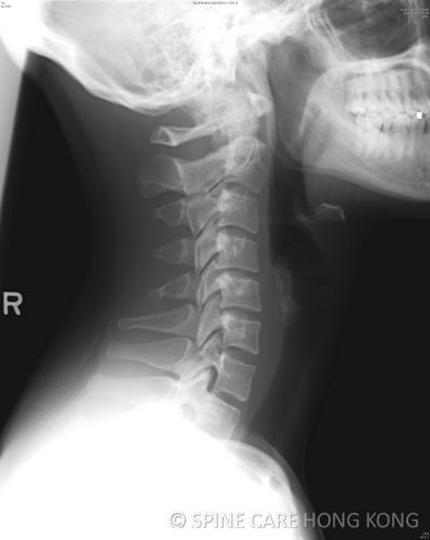

Spine Care Hk

Photos of Spine Care Hk